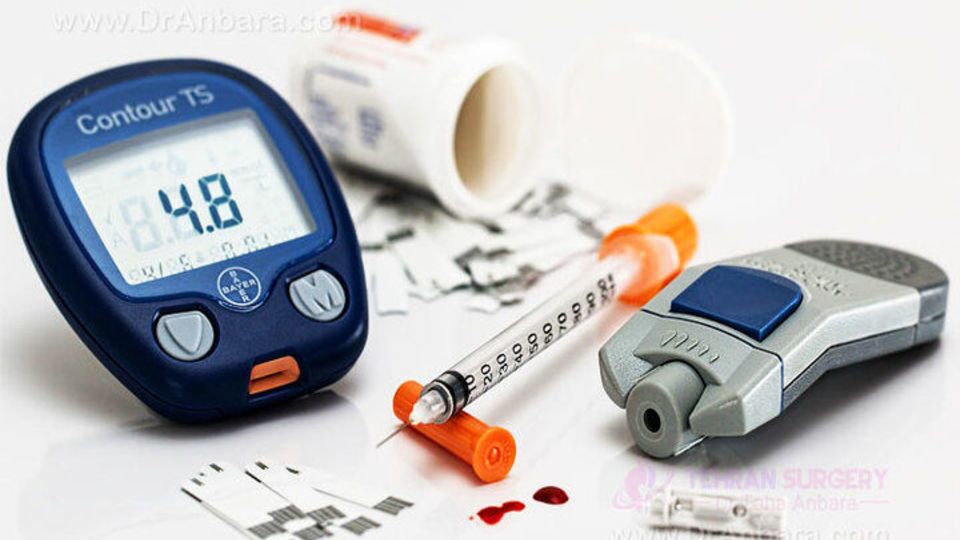

نوع جدیدی از دیابت به رسمیت شناخته شد

آفتاب نیوز : فدراسیون بین المللی دیابت (IDF) پس از تحقیقات مردیت هاوکینز بنیانگذار مدیر انستیتو جهانی دیابت در کالج…